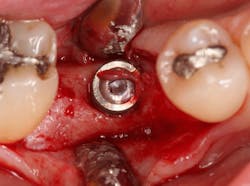

At this point, releasing incisions (vertical incisions and/or periosteal releasing incisions) can be made to achieve primary closure or to leave the membrane exposed and let the area heal by secondary intention. With the Ossix Plus membrane’s increased resistance to bacterial collagenase and the stresses of the oral environment, I feel comfortable leaving the membrane exposed and allowing the attached gingiva to heal over the membrane. This will result in reduced swelling and discomfort during healing, and there is less risk of damaging the mental nerve as it exits the mental foramen and fans laterally into the tissue. Attached gingiva around an implant will facilitate a more accurate impression, easier delivery of the restoration (and increased resistance to cement penetrating subgingivally), and easier hygiene for the patient. Also, when the implant is uncovered after healing, a tissue punch can be used, and there will generally be no need for a flap and sutures, thus improving the patient experience. Conversely, primary closure is imperative when performing a lateral or vertical ridge augmentation with or without simultaneous implant placement. Generally, when the extraction socket walls are intact, leaving the membrane exposed and allowing attached gingiva to grow over the membrane is predictable.

In this case, I placed an autogenous fibrin clot, which was isolated from the fractionated blood draw, over the Ossix Plus membrane and sutured, without obtaining primary closure, using a CV-5 Gore-Tex (W.L. Gore & Associates Inc.). This technique is designed to help facilitate the formation of a blood clot over the Ossix Plus membrane. It can be used with the addition of a collagen plug over the membrane, or you can just suture and allow a natural clot to form.